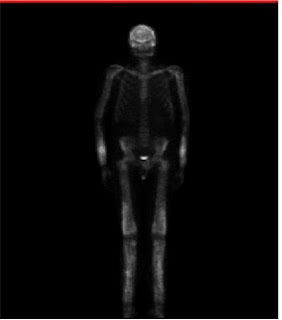

Gammagrafía ósea: detecta un aumento de la actividad osteoblástica en las regiones afectadas y esta actividad puede ser detectada incluso antes de la afectación radiológica

Gammagrafía ósea característica de la enfermedad de Camurati-Engelmann en la que podemos observar un aumento de la captación simétrica en las diáfisis de los huesos largos (fémur, tibia, húmero, cúbito) y de la pelvis.